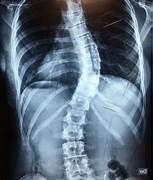

Para diagnosticar la escoliosis se ha de hacer una radiografía de la columna vertebral completa, de frente y de perfil. En la radiografía de frente de la columna es donde se verá si existe esta curvatura en la columna lo suficientemente importante como para considerarla una escoliosis.

Vista de frente la columna se observa con una alineación perfecta.

La escoliosis es la alteración de esta configuración normal.